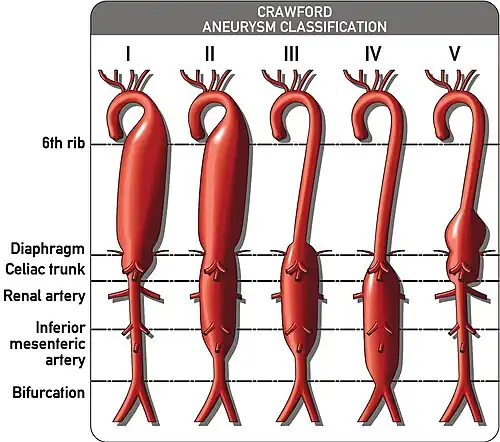

Thoroacoabdominal aneurysms are those which span the chest and abdominal cavities. The Crawford classification was developed and describes five types of thoracoabdominal aneurysms.[9]

The Crawford Classification (Extent I-IV) and the Safi modification (Extent V) for thoracoabdominal aortic aneurysms is pictured above.

The Crawford Classification (Extent I-IV) and the Safi modification (Extent V) for thoracoabdominal aortic aneurysms is pictured above.